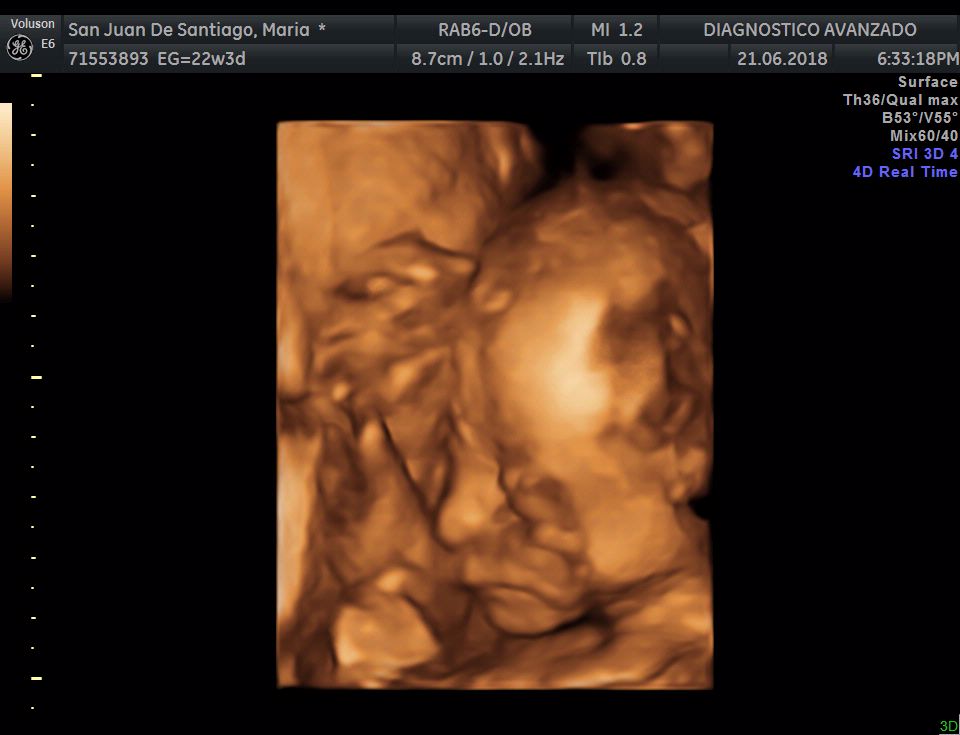

¡Hola a todos! Hoy hemos ido a hacer la tradicional ecografía 3D de la niña, os dejamos todo el material (aunque es un poco demasiado).